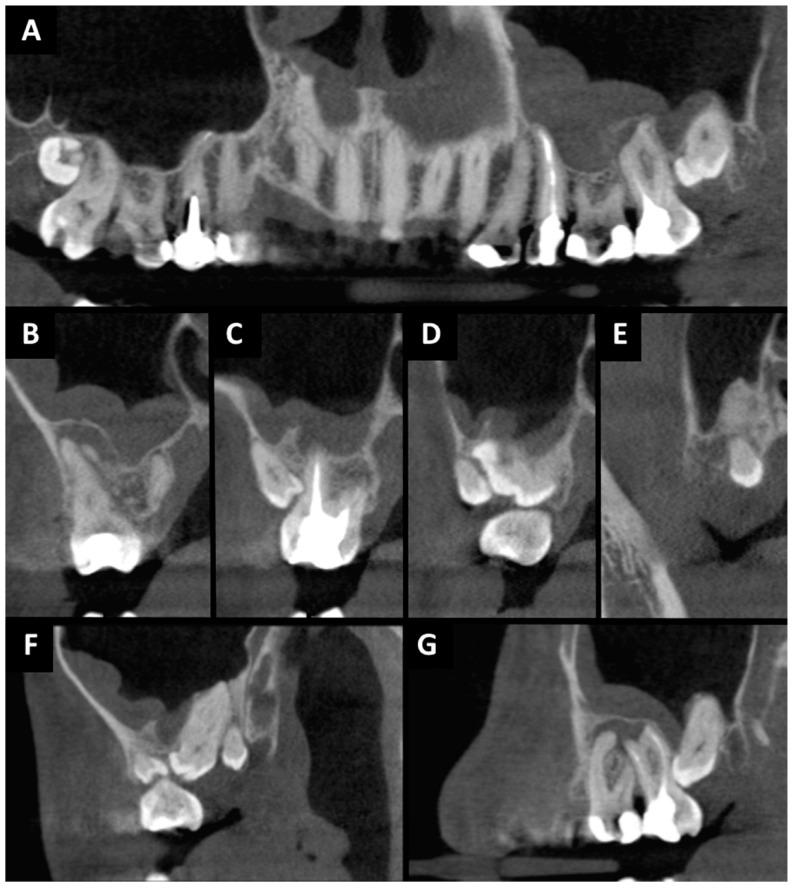

Chronic odontogenic maxillary sinusitis (COMS), a prolonged inflammation of the maxillary sinus lasting over 12 weeks, is often a result of periapical lesions, marginal periodontitis, and complications like oro-antral communication (OAC) and fistula (OAF). OAC, commonly emerging post-teeth extraction in the lateral maxilla, lacks documented treatments using advanced platelet-rich fibrin (A-PRF). This study evaluates A-PRF's efficacy in treating COMS and immediately sealing extensive OAC. A case of a 28-year-old male with COMS linked to a periapical lesion and supernumerary molars is presented. Treatment involved extracting specific teeth while preserving adjacent ones and using A-PRF for immediate OAC closure. A-PRF, enriched with growth factors, was pivotal in healing, showcasing enhanced tissue regeneration, pain reduction, and faster recovery. The findings suggest A-PRF as an effective adjunct in treating extensive OAC and COMS, proposing its inclusion in standard treatment protocols. This study underscores A-PRF's potential in improving outcomes for patients with COMS and related complications.

慢性牙源性上颌窦炎(COMS)是上颌窦持续超过12周的长期炎症,通常是根尖周病变、边缘性牙周炎以及诸如口腔上颌窦交通(OAC)和瘘管(OAF)等并发症的结果。OAC常见于上颌外侧牙齿拔除后,目前缺乏关于使用高级富血小板纤维蛋白(A-PRF)进行治疗的文献记载。本研究评估A-PRF在治疗COMS和即刻封闭广泛OAC方面的疗效。报告了一例28岁男性患者,其COMS与根尖周病变和多生磨牙有关。治疗包括拔除特定牙齿同时保留相邻牙齿,并使用A-PRF即刻封闭OAC。富含生长因子的A-PRF在愈合过程中起关键作用,表现出增强的组织再生、疼痛减轻和恢复加快。研究结果表明A-PRF是治疗广泛OAC和COMS的有效辅助手段,建议将其纳入标准治疗方案。本研究强调了A-PRF在改善COMS及相关并发症患者治疗效果方面的潜力。